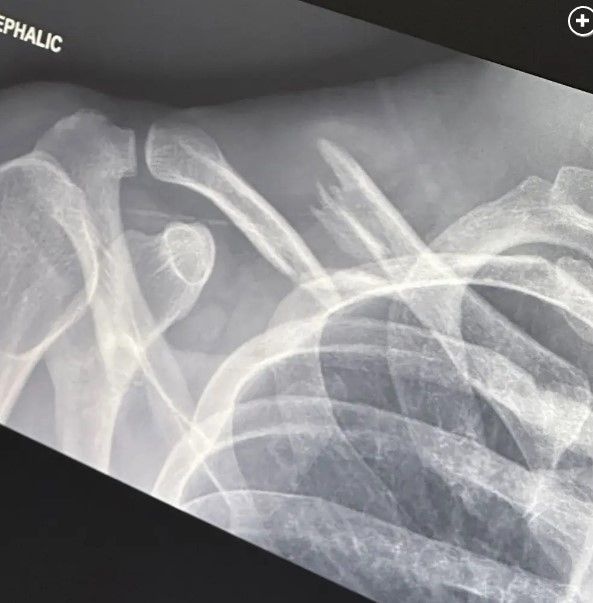

Την περασμένη εβδομάδα νεαρός καλλιτέχνης έπεσε ενώ οδηγούσε το ηλεκτρονικό του ποδήλατο και υπέστη κάταγμα κλείδας και αγκώνα. Ο 25χρονος μοιράστηκε μια ακτινογραφία του σε Instagram-story, η οποία έδειχνε ένα από τα κατάγματά του.

«Την περασμένη Παρασκευή, είχα τη χαρά να συντρίψω το ηλεκτρικό μου ποδήλατο, να πετάξω πάνω από το τιμόνι και να κατεδαφίσω εντελώς την κλείδα μου καθώς και να υποστώ ένα ακτινωτό κάταγμα κεφαλής στον δεξιό μου αγκώνα», έγραψε ο παραγωγός.

«Η σοβαρότητα της μετατόπισης της κλείδας μου σήμαινε ότι χρειάστηκα χειρουργική επέμβαση από την οποία αναρρώνω και αισθάνομαι υπέροχα!», πρόσθεσε ο Finneas.